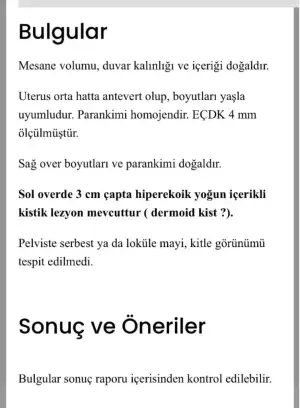

15 mayısta aşılamayla 31 mayısta hamile olduğumu öğrendim. Kese var bebek görünüyor görünmüyor derken 19 Temmuz’da boş gebelik sebebiyle kürtaj oldum, şu an başka bir ildeyim kontrole gittim en son radyolojide yapılan muayenede aşağıdaki sonucu aldım, doktorun çektiği ultrasonda da net bir şekilde görünüyor, doktor izne ayrılmış sonuçları gösteremedim, daha kendi doktoruma görünmeme de epey vakit var yine içime bir kurt düştü. Başına gelen veya bu durumu anlayabilen varsa yorum yapabilirse sevinirim

15 mayısta aşılamayla 31 mayısta hamile olduğumu öğrendim. Kese var bebek görünüyor görünmüyor derken 19 Temmuz’da boş gebelik sebebiyle kürtaj oldum, şu an başka bir ildeyim kontrole gittim en son radyolojide yapılan muayenede aşağıdaki sonucu aldım, doktorun çektiği ultrasonda da net bir şekilde görünüyor, doktor izne ayrılmış sonuçları gösteremedim, daha kendi doktoruma görünmeme de epey vakit var yine içime bir kurt düştü. Başına gelen veya bu durumu anlayabilen varsa yorum yapabilirse sevinirim